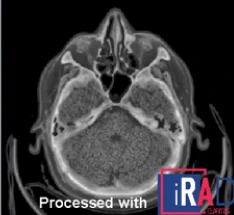

Processamento avançado de TC com redução significativa de ruído e melhoria da qualidade da imagem para diagnósticos mais precisos, permitindo protocolos de baixa dose sem comprometer a qualidade.

Otimização de imagens de RM com melhoria de resolução, redução de artefatos e melhor definição de tecidos moles, proporcionando maior confiança diagnóstica em todas as sequências.

Original

Processado com iRAD